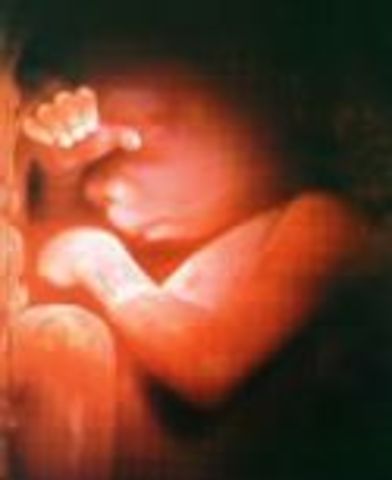

• week 26

week 26

1.The fetus makes breathing movements, but there is no air in the lungs yet

2.Hands are active and muscle coordination is such that they can get a thumb into the mouth

• week27